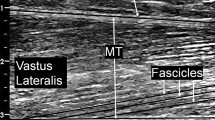

Muscle size

The maximum CSA of knee extensor and plantar flexor muscles from the right limbs were assessed once before (BDC-2), and once following BR (R + 0) using Magnetic Resonance Imaging (Siemens Sonata scanner) at 1.5 Tesla using a spin echo sequence (TR = 28.00 ms, TE = 4.78 ms). Axial images with 3 mm (thigh) or 2 mm (lower leg) slice thickness were acquired with a matrix of 256 × 224 pixels of 1.0 × 1.0 mm pixel size. Subjects were positioned with their thighs in the horizontal plane, and foot restraints were used for fixation. To prevent fluid shifts from influencing CSA secondary to a change in body position, subjects remained supine for 30 min before imaging started. The knee extensor and plantar flexor muscle were each manually encircled by one operator blinded to both the session and intervention, and CSA was calculated using semi-automated SliceOmatic 4.3 software (Tomovision, Magog, Canada). Sliding averages of CSA values were calculated for three successive slides (Mulder et al. 2006) and the highest mean value was used as maximum CSA for further evaluation.

Motor unit activity in the m. vastus laterals during knee extension and in the m. gastrocnemius medialis during plantar flexion was recorded with bipolar differential electromyography (EMG) using a Noraxon MyoSystem 1400A and Ag–AgCl surface electrodes directly connected with pre-amplifiers. Before applying the electrodes, the skin was shaved, cleaned and scrubbed with sandpaper. Skin–electrode resistance was checked for being lower than 10 kΩ and the skin was re-prepared if needed. The correct position of the electrodes was verified by M-wave assessments and this position was retained across the study using cutaneous ink marks. To also ensure consistency across campaigns, individual EMG templates (transparent plastic sheets with identified landmarks and electrode locations) were constructed during the initial pretest and subsequently used prior to all tests. Torque and EMG signals were digitized at 1,000 Hz using Noraxon software and processed by customized software. For each MVC trial, the peak torque value of a 0.5 s interval was assessed and EMG amplitude (RMS) was averaged for that time. The contraction that yielded the highest peak torque value at any of the angles was finally selected for comparisons. To discriminate between changes in RMS due to alterations in neural drive from changes due to alterations in peripheral factors, we normalized the RMS to the RMS of the M-wave (Arabadzhiev et al. 2010). RMS and median frequency (FM) during the knee extensor fatiguing contraction were assessed over the first 2 s and the 2 s immediately preceding task failure.